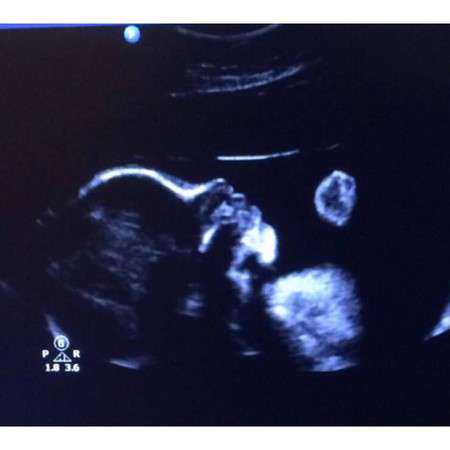

3.孕7周:心脏搏动明显,可显示胎体头极和尾极,并见小肢芽,这时候三维超声会看见宝宝像一个小蚕豆一样。

4.孕8周:初具人形,各部分迅速发展,头颅、躯干、四肢显示越来越清楚。